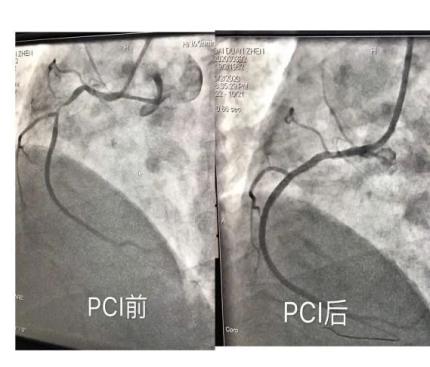

立即为患者行“冠脉造影”

显示右冠状动脉中段99%

局限性狭窄病变

综合病情及检查结果

患者需立即急诊行“PCI” 术

通俗地说,就是“放支架”